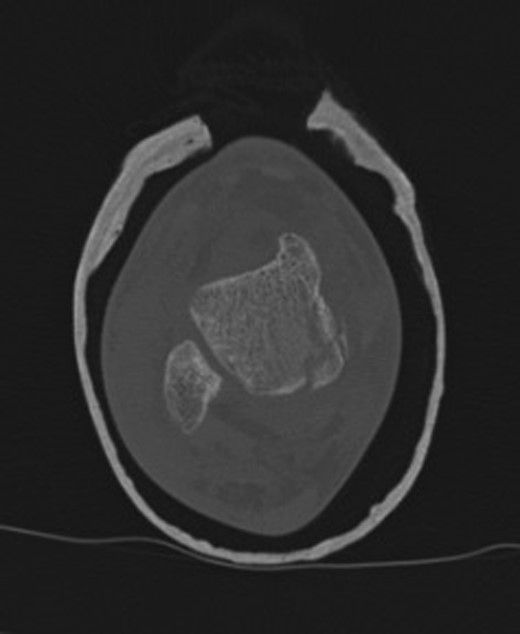

At 12 weeks follow-up, the patient was weight bearing comfortably with near full range of movement. A repeat CT and MRI scan showed no evidence of displacement of the fracture fragments with good evidence of talus fracture healing. MRI revealed reduction in bone marrow signal changes with no evidence of subchondral collapse (Figs 4 and 5).

12-week follow-up CT axial view of the talus confirms no further displacement of the fracture nor any evidence of osteonecrosis. There is radiological evidence of callus bridging the fracture site.